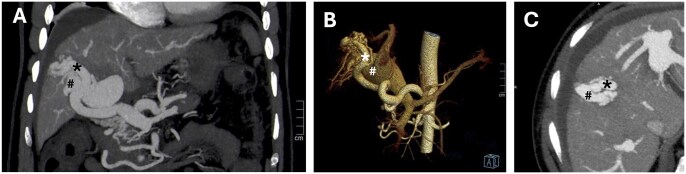

经颈静脉肝内门静脉-全身分流术(TIPS)是治疗门静脉高压(PH)并发症的有效方法。在这里,我们报告了一个复杂的病例,由于胃食管静脉曲张破裂引起的出血性休克,在PH的背景下,最初是由特发性的,可能是先天性的,高流量肝内动脉门静脉瘘(IAPFs)持续,然后是广泛的肠缺血。虽然iapf的闭塞有可能控制内脏动脉血液进入门静脉循环,但它无法控制PH相关出血,因此需要放置补补性TIPS。门静脉压力梯度在IAPFs闭塞后持续显著增加,表明独立的肝内成分导致ph。此外,肝脏组织学显示,长期IAPFs继发于肝实质的窦前/窦前阻塞反应,导致肝内ph的发作。基于这些原因,联合介入方法导致了难愈的门静脉高压出血的解决。避免弥漫性肠梗死的致命性发展。

Transjugular intra-hepatic porto-systemic shunt (TIPS) is a proven strategy for the management of portal hypertension (PH) complications. Here, we report on a complex case of haemorrhagic shock due to the rupture of gastro-oesophageal varices in the context of PH originally sustained by idiopathic, likely congenital, high-flow intrahepatic arterioportal fistulas (IAPFs) preceded by extensive bowel ischaemia. While the occlusion of the IAPFs potentially controlled the steal of arterial splanchnic blood into the portal circulation, it failed to manage PH related bleeding, necessitating the placement of a salvage TIPS. Porta-caval pressure gradient persisted markedly increased after IAPFs occlusion, indicating an independent intra-hepatic component causing PH. Moreover, hepatic histology demonstrated a pre-sinusoidal/sinusoidal barrage response of the hepatic parenchyma secondary to long-standing IAPFs, causing the onset of an intra-hepatic component of PH. For these reasons, the combined interventional approach led to resolution of the refractory portal hypertensive bleeding, avoiding fatal evolution of diffuse bowel infarction.